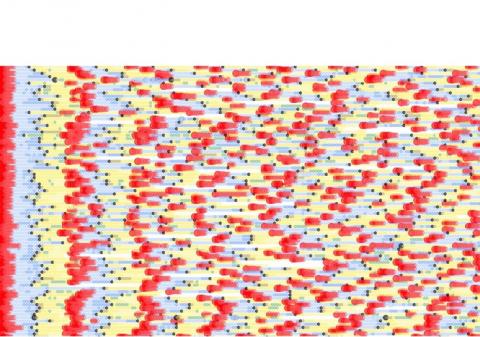

Cette étude est la première à montrer l’intérêt de ces nouveaux outils de suivi individuel et épidémiologique en examinant à la fois les données de visites gynécologiques et d’utilisations de ces applications au niveau de la population pour déterminer et comparer leur précision dans l'évaluation de la santé menstruelle et de la fertilité. L’étude passe ainsi par une modélisation globale des données recueillies (Voir visuel : chaque ligne est un utilisateur, chaque point est un jour. Les couleurs des points correspondant à différents états biologiques).